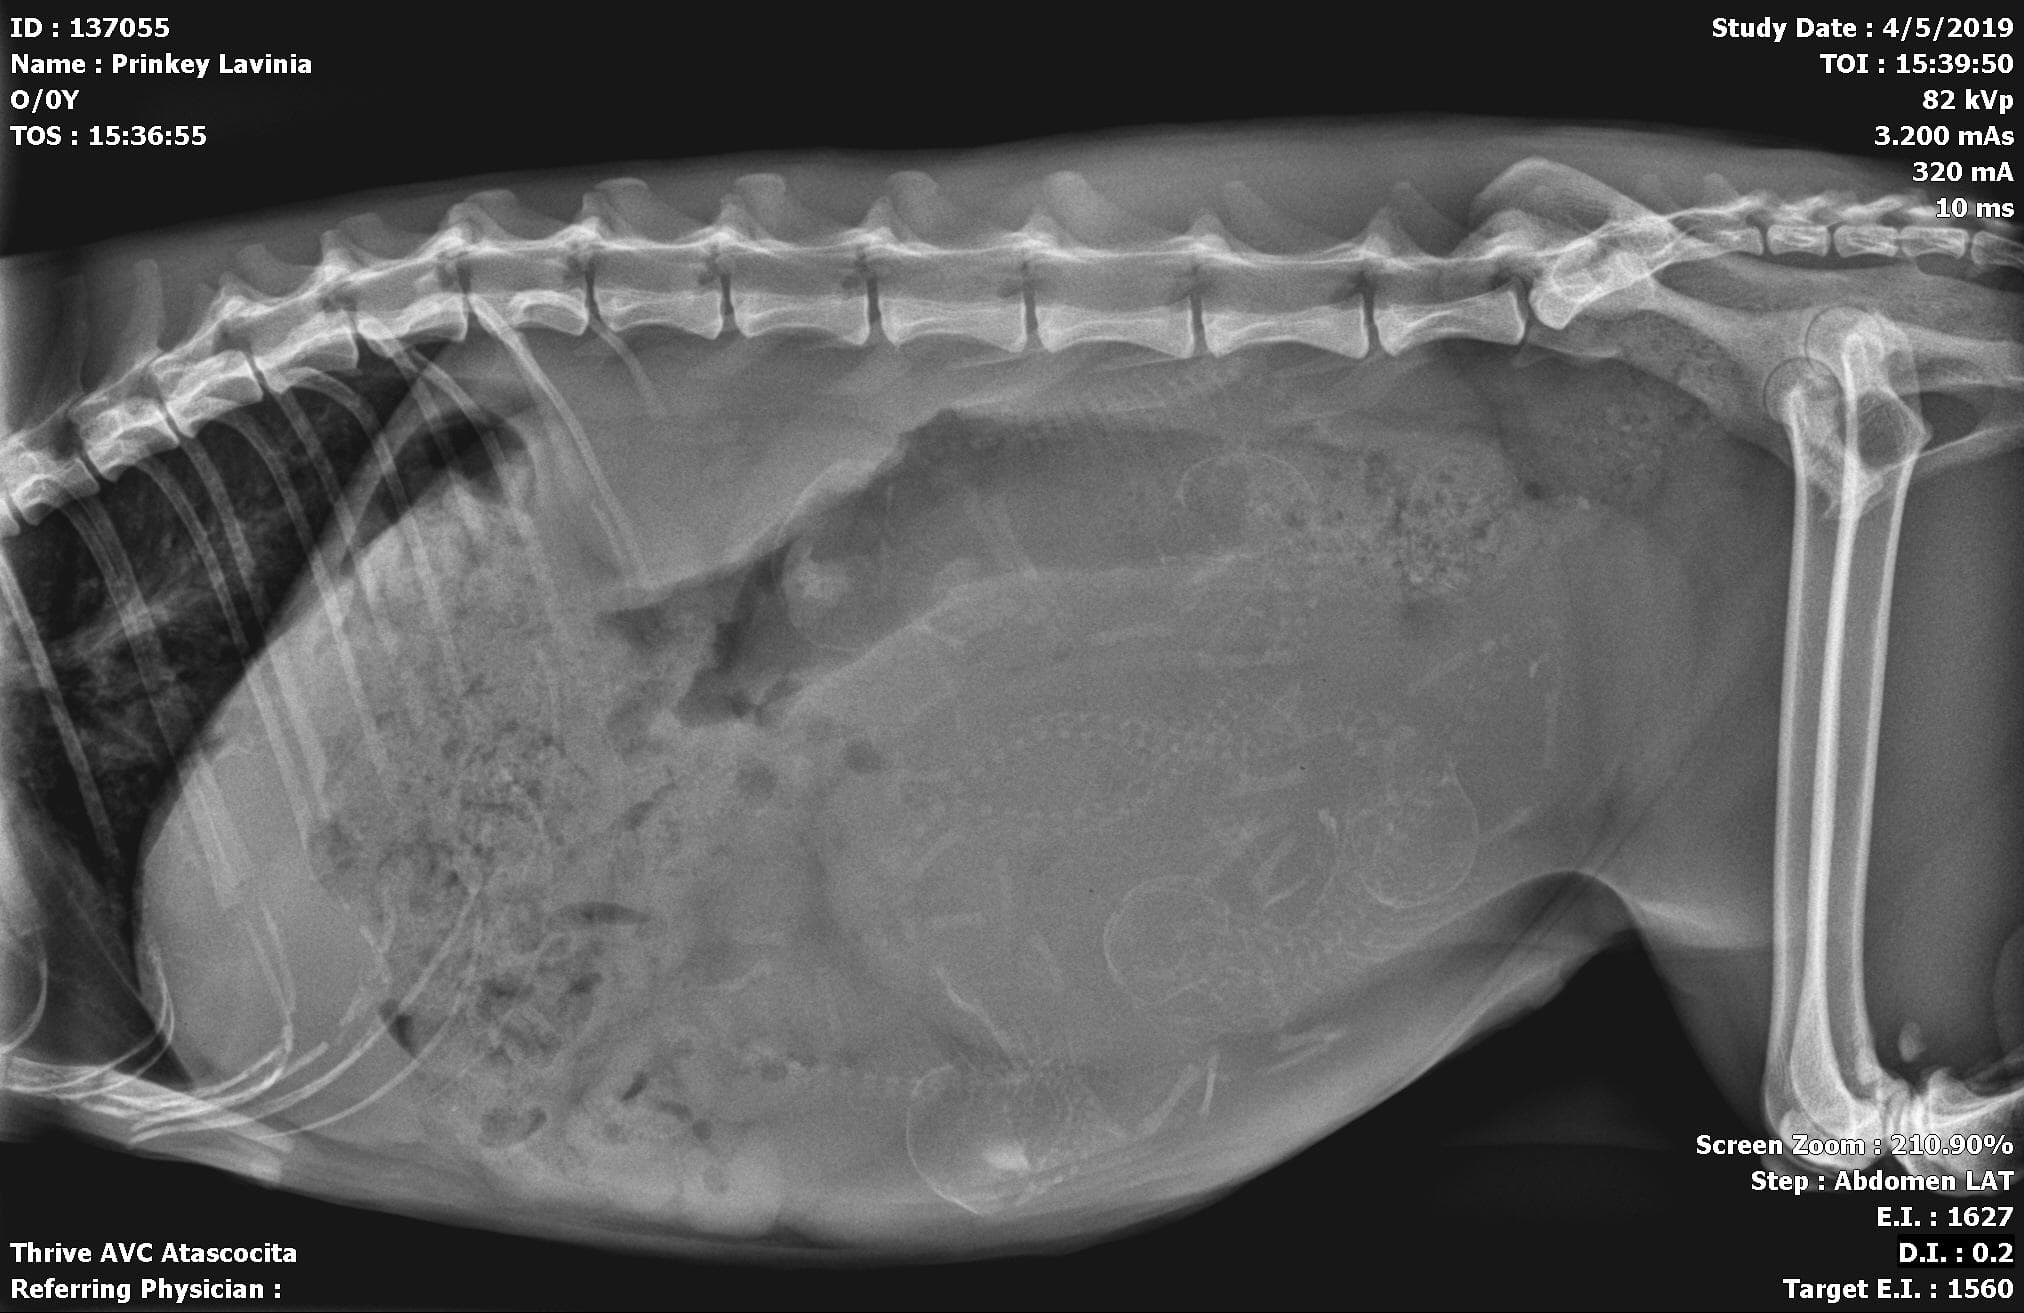

My Sphynx gave birth to 5 healthy babies Monday morning (and some late Sunday night) The X-ray showed 5 possibly 6 babies. I felt like i felt and saw another still in there but she hasn’t pushed since she birthed the last one. She’s eating and drinking fine Acting completely normal. My er vet said to come in if she acts unusual but I’m worried that she won’t pass the last one And would an oxytocin injection possibly fix the problem? I heard about interrupted labor so maybe it’s that?

I recommend you call your vet and have Lavinia examined to make sure all is well. They may recommend another x-ray just to make sure there are no complications and no kittens left in the birth canal.